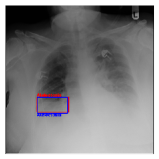

IV-D Investigation of the generated heatmap

By using the training result of the Adaptive DBN, the heatmap images were generated in addition to detection of B-Box. The heatmaps in Fig. 10 to Fig. 14 show the detection result of B-Box and the generated heatmap for some images. The red and blue rectangles in the image are given B-Box and detected B-Box, respectively. A heatmap is represented by the continuous value of range [0,255]0255[0,255], where the color map is jet color array (red means high value, while blue means small value). The diseases for detected B-Boxes in Fig. 10 to Fig. 14 were as follows; Infiltration (Fig. 10), Mass (Fig. 10), Nodule (Fig. 10), Mass and Pneumothorax (Fig. 10), Atelectasis (Fig. 14), Infiltration (Fig. 14), Atelectasis (Fig. 14), Atelectasis (Fig. 14).

Overall, the red area of the generated heatmap included in both the given B-Box and detected B-Box. On the other hand, the blue or yellow areas didn’t include in these B-Boxes. This tendency was seen in not only large diseases (e.g. Cardiomegaly or Infiltration) such as Fig. 10, but also small diseases (e.g. Mass or Nodule) such as Fig. 10. We consider that the experimental results caused by the discrete heatmap with binary output of final RBM layer instead of continuous heatmap. As a result, the red regions represents localization with strong relation to diseases and blue regions represents localization with weak relation. The generated heatmap shows the portion with strong relation more clearly.

In Fig. 14, the detected B-Box was located at a little upper than the given B-Box. The red area of the heatmap was also at upper position. The detected B-Box is slightly larger than the given B-Box. The detected B-Boxes are almost same as the given B-Boxes except the different size. For better detection capability, the feature of the generated heatmap will be investigated with the medical specialists.